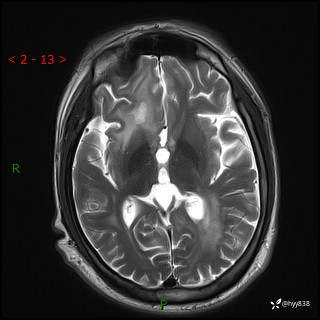

辅助检查:MRI

MRI T2WI